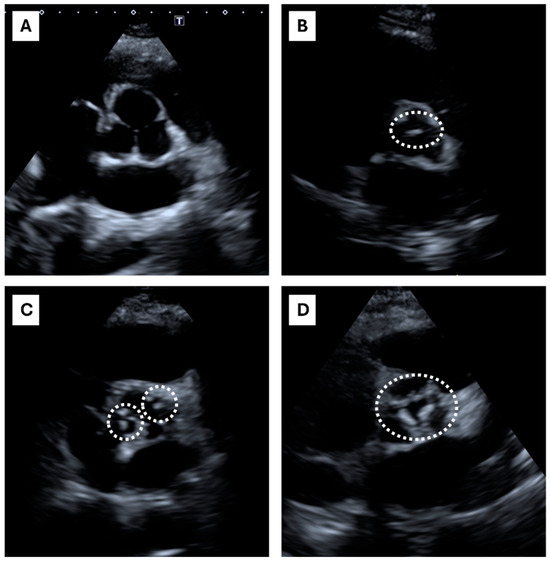

Echocardiographic Calcium Score of Aortic Valve Correlates with Coronary Artery Calcium Score in Heterozygous Familial Hypercholesterolemia

by Angelo Baldassare Cefalù, Emilio Nardi, Antonina Giammanco, Carola Maria Gagliardo, Carlo Maria Barbagallo, Ludovico La Grutta, Patrizia Toia, Federica Brucato, Chiara Scrimali, Teresa Maria Grazia Fasciana, Rossella Spina, Marina Lanza, Francesco Vitale, Davide Noto and Maurizio Averna

Life 2025, 15(3), 506; https://doi.org/10.3390/life15030506 - 20 Mar 2025

Background: Patients with heterozygous familial hypercholesterolemia (HeFH) are at a high risk of atherosclerotic cardiovascular disease. The coronary artery calcification (CAC) score by the Ct-scan Agatston calcium score (ACS) > 100 classifies FH at a higher risk. The echocardiographic calcium score (ECS) evaluates [...] Read more.

Background: Patients with heterozygous familial hypercholesterolemia (HeFH) are at a high risk of atherosclerotic cardiovascular disease. The coronary artery calcification (CAC) score by the Ct-scan Agatston calcium score (ACS) > 100 classifies FH at a higher risk. The echocardiographic calcium score (ECS) evaluates aortic valve calcifications and is considered a good predictor of the atherosclerotic burden and cardiovascular outcome. Objective: To test the ECS as a predictor of ACS > 100 in a HeFH cohort. Methods: A coronary calcium CT scan with the calculation of ACS and an at rest-transthoracic echocardiogram with ECS evaluation were performed in 81 HeFH patients. Patients were divided into two groups according to the ACS: high-risk ACS patients (High-ACS) with Agatston value > 100 and low risk ACS patients (Low-ACS) with Agatston value ≤ 100. Patients were stratified according to ECS = 0 or ECS > 0. Results: High-ACS patients were older than Low-ACS patients; BMI, waist circumference, and blood systolic pressure were significantly higher (p < 0.001) in High-ACS patients. The ECS predicted an ACS > 100 with sensitivity = 0.84, specificity = 0.89, accuracy = 0.86, and precision = 0.76. Conclusions: The ECS could be a good surrogate of a coronary calcium CT scan for ACS evaluation in the specific subset of HeFH patients. Full article

Show Figures

Figure 1